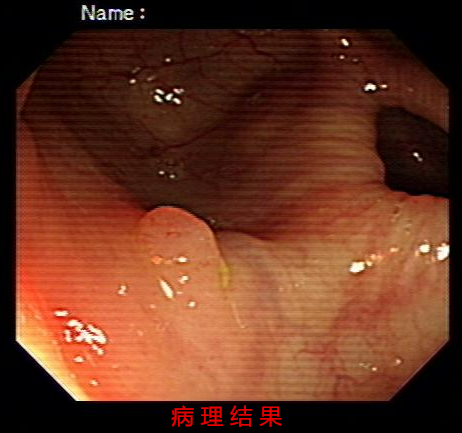

�������ү��Ž��ܳ�����飬���������ж���س�ҽԺ�������ν�����˽���ƽ��������ϰ�ߺ�������ȥ������飬�������ү�������ж�öϢ�⡣���ү��ʱ����ܺ�ڣ�Ϊʲô�����������ҽ����Ա�ĵ绰�����Ķ����ҽ����Աһֱ��ֲ�и�ĸ��Լ���绰���Լ�����Ϊҽ����Ա�ں����Լ�����һֱ��Ϊ�Լ�û�������ϸ����꣬��֢�϶�Ҳ��Զ��!С��Ҳ���ѱ�ס��!

�����������֮�������ʾ���ү�����˳�Ϣ�⣬Ŀǰ��û���ֶ�����